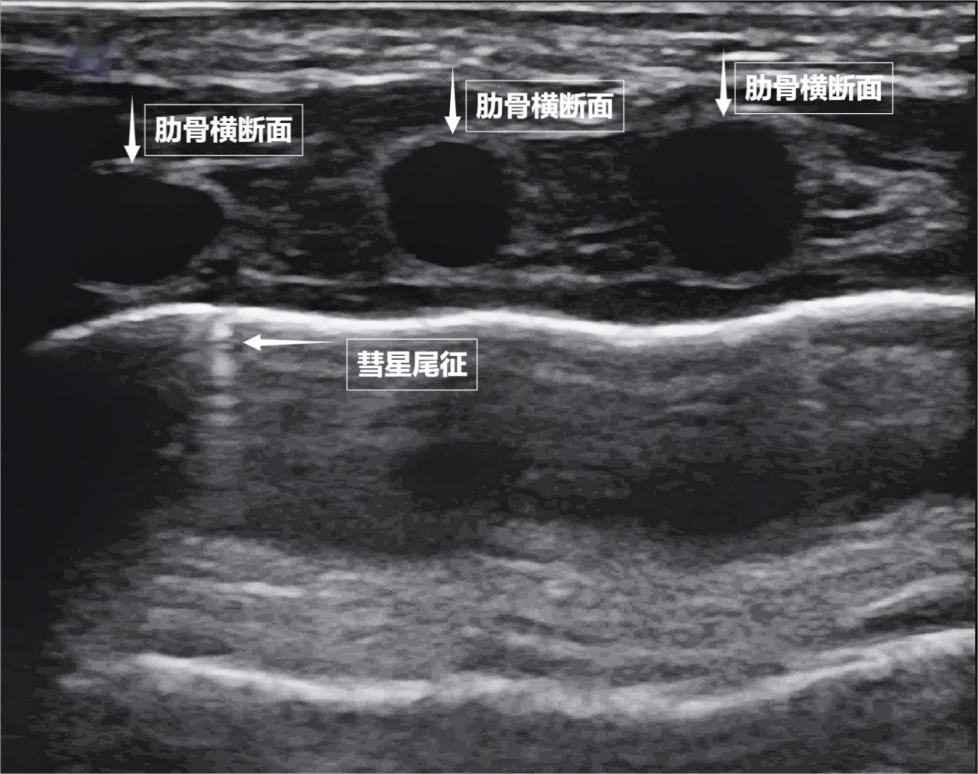

第二景:“沙滩与浪花”——肺滑动征

如果我们把超声图像调成实时动态模式,把“照片”变成“电影”,更神奇的一幕出现了。随着呼吸,胸膜线会随胸廓运动轻柔滑动,这就是“肺滑动征”。它意味着肺与胸壁正紧密相依、自由顺畅地呼吸。若肺与胸壁间有气胸或胸腔积液,这种滑动会消失。有时,在胸膜线下方还会出现细小的亮白色闪烁点,称为“彗星尾征”(见下图)。其少量、孤立出现时,通常是正常肺小叶间隔的反射,无需担心。

▲图为正常新生儿肺部超声表现